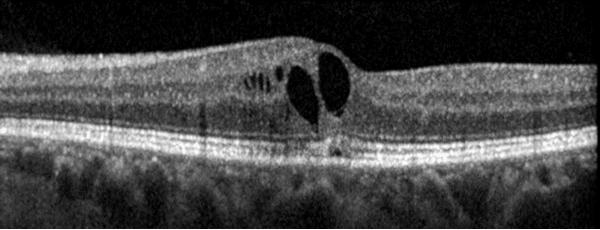

Macular Edema

As with other conditions listed here, the location of macular edema can lead to metamorphopsia, decreased visual acuity, and other central vision changes. However, this patient does not have a history of vascular conditions that would predispose her to the development of macular edema, such as diabetes or retinal vein occlusion. While she does have a history of cystoid macular edema (CME), her current imaging does not demonstrate significant edema. An example of chronic CME seen on OCT is pictured below.